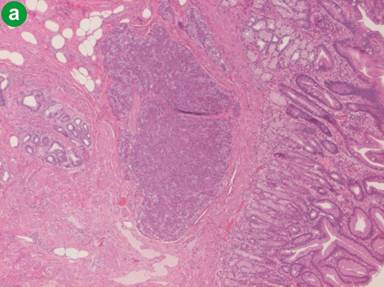

A 38-year-old male patient presented to the emergency room due to acute epigastric pain, nausea and vomiting. Physical examination revealed tenderness in the upper abdomen. Body temperature was 37.3°C. C-reactive protein was 113 mg/L (reference range: 0-3 mg/L) and his white blood cell count was raised (15.5 x109/L; reference range: 3.5-8.8 x109/L). Renal and liver function tests and serum pancreatic amylase were normal. He was otherwise healthy and was not taking any medications. Upper gastrointestinal endoscopy showed a subepithelial lesion in the gastric antrum (Figure 1). Abdominal computed tomography scan revealed a heterogeneous 4 cm malignant-looking lesion in the gastric antrum with suspected invasion of the perigastric fat (Figure 2). Endoscopic ultrasound (EUS) confirmed the presence of a subepithelial lesion in the antrum, that had heterogeneous appearance and involved all subepithelial layers of the gastric wall (Figure 3). An EUS-led fine needle aspiration (FNA) showed inflammatory cells only. The patient recovered symptomatically and blood tests normalized within 5 days. However, on the grounds of the imaging findings, malignancy could not be excluded and distal gastrectomy was performed. Histopathology of the surgical specimen confirmed the presence of ectopic pancreas in the gastric antrum (Figure 4a) but showed no cancer. However, there was both chronic and acute inflammation with neutrophil infiltration (Figure 4b). Twelve months following surgery he was asymptomatic.

Figure 4. Histopathology of the surgical specimen showed the presence of acini and ductal structures in the proximity of gastric mucosa, i.e. gastric ectopic pancreas (H&E x4) (a.) and acute and chronic inflammation with reactive ductal changes (H&E x60) (b.). |